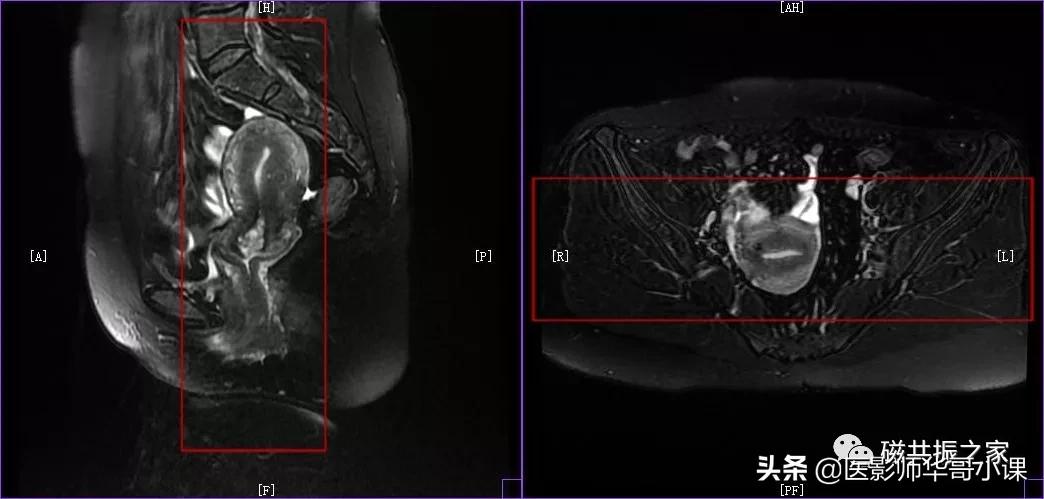

子宫MRI扫描前应先行1-2个大范围的 全盆腔 扫描序列,通常为大范围的T1WI和T2WI 压脂序列;在冠状位和矢状位上定位,按照常规的横轴位扫描即可。

行大范围扫描的目的:

1.了解盆腔内病变的大体情况。

2.视察盆腔内出血、转移、周围侵犯等情况。